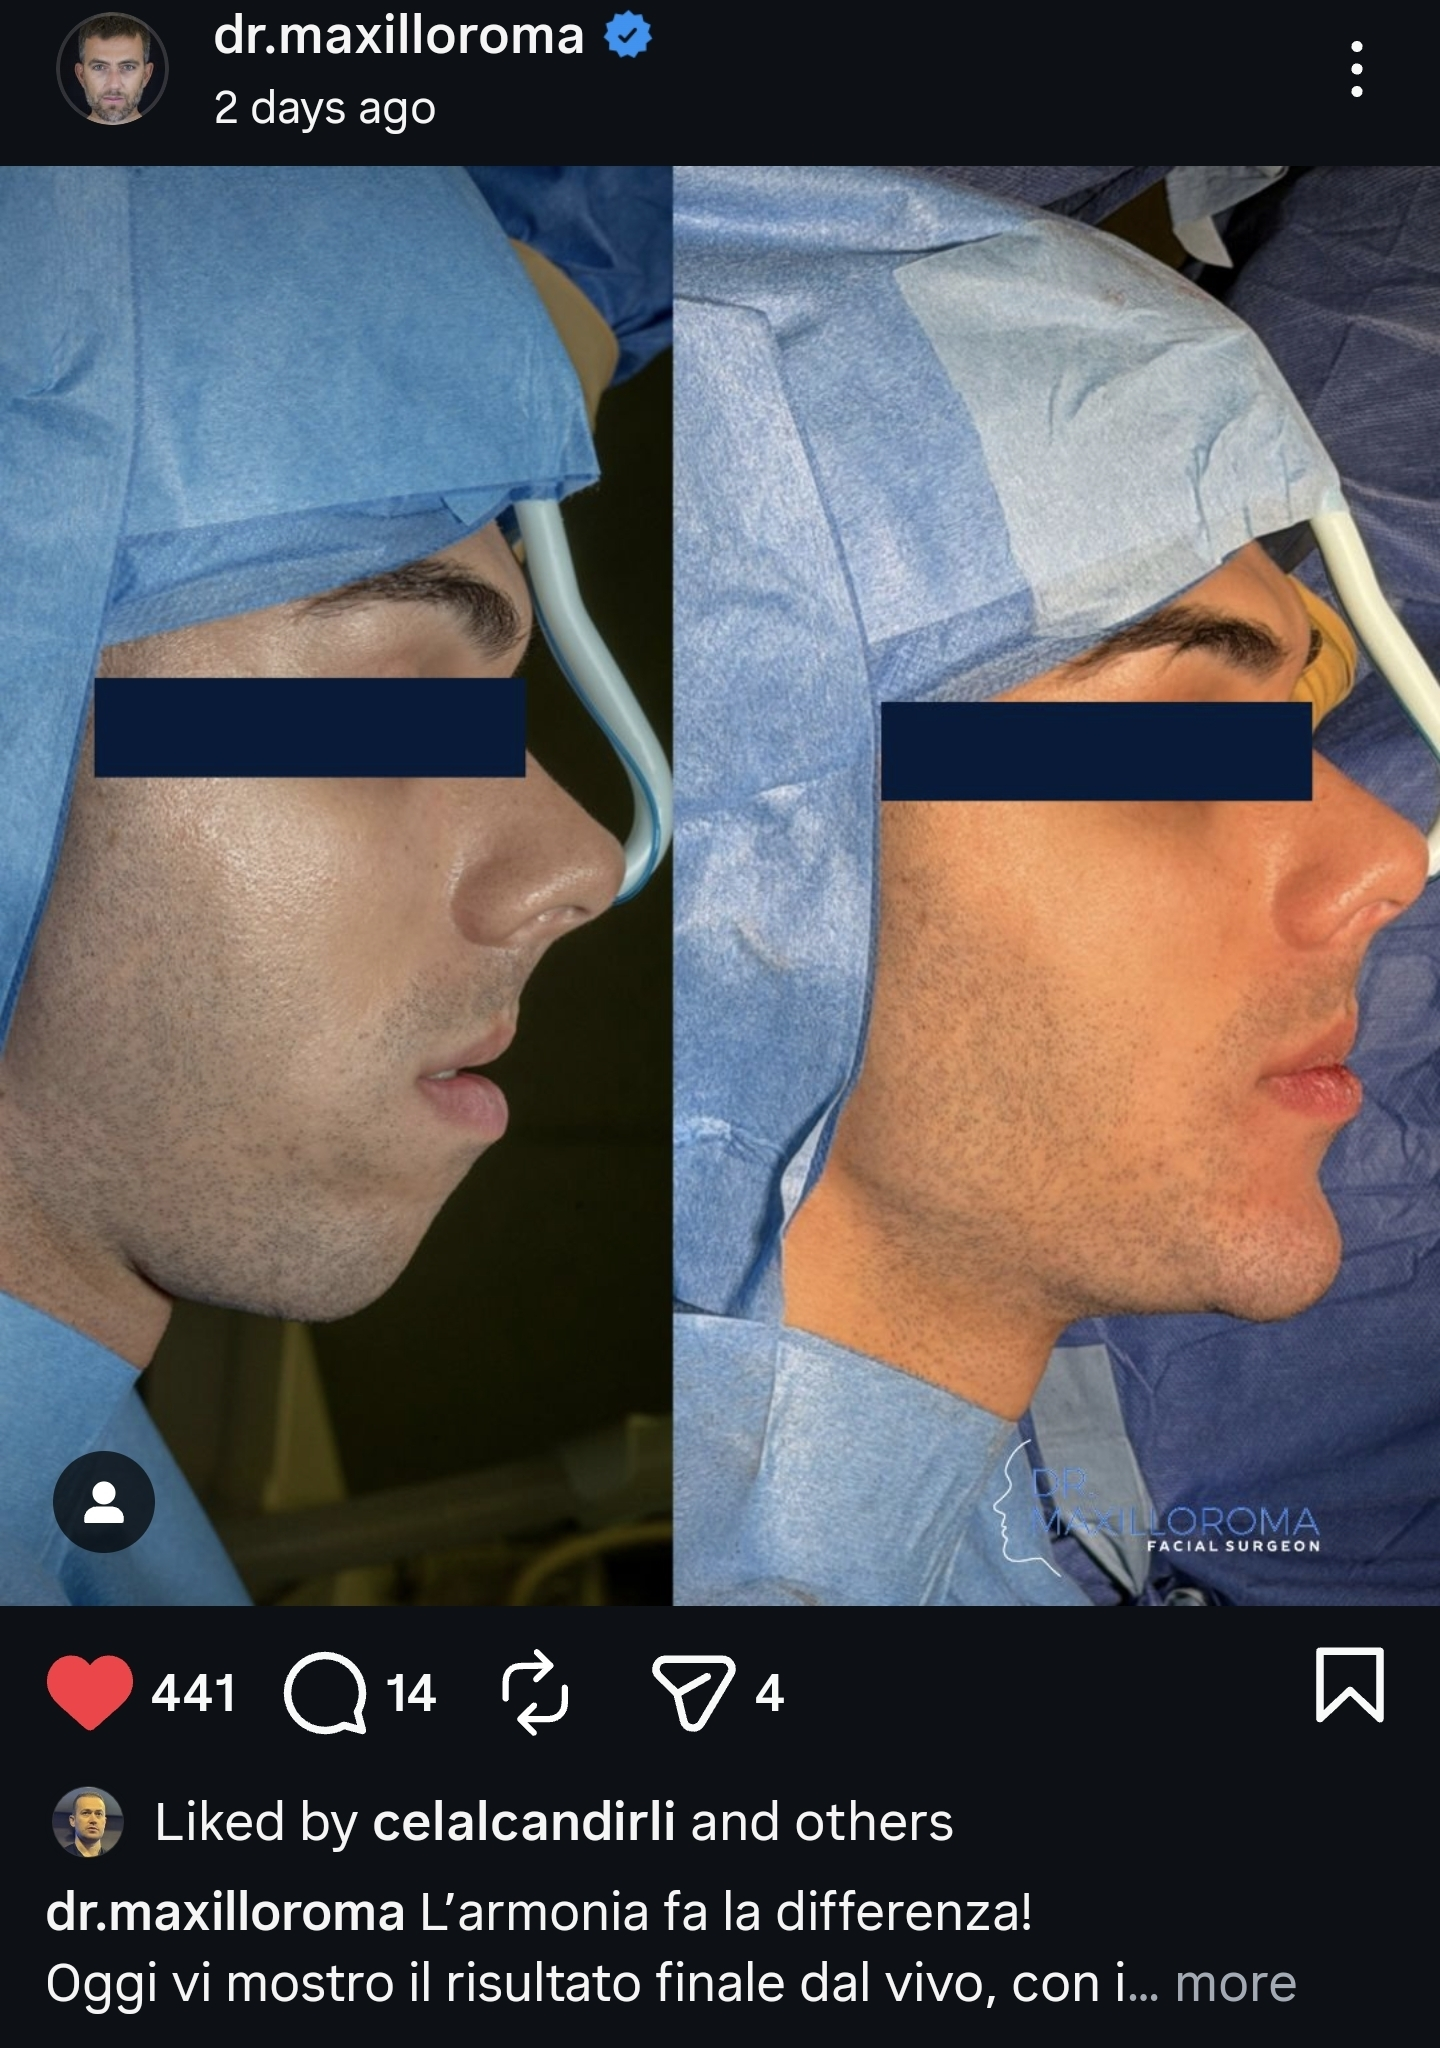

Case #1:

16mm genio-only projection with jawline implants. Clearly a trimax case, but for some bizarre reason, Ramieri chose to only do a genio instead. Note the deep mentolabial fold and the bunching around the submental from the transition between the chin and the rest of the mandible.

The post was uploaded to Instagram, but now seems to be deleted. The fact that this was considered a good result worthy of posting is kind of concerning ngl. That being said, 16mm is a massive movement when the whole mandible is clearly fcked in this case... so aesthetic complications are not surprising.